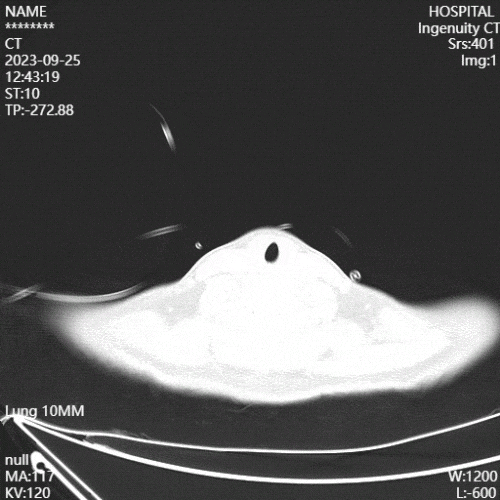

(5)康复措施及效果:复查影像学可见患者肺部炎性病变较前减少。

图片